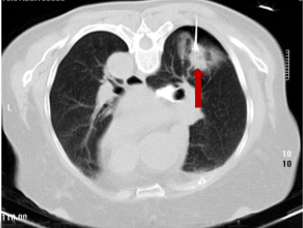

术后9+年,患者再次到我院复查胸部CT,发现右上肺上方(尖段)新增结节,诊断为转移瘤,征得患者及家属同意后,再次为患者实施右上肺尖段新增结节碘125粒子植入技术,进一步为患者稳定病灶。

术后9+年复查

右上肺尖段新增结节碘125粒子植入